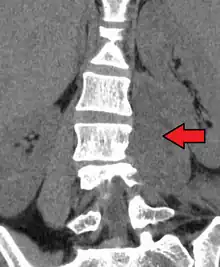

Psoas muscle abscess

Paraspinal abscess in the psoas muscle

Psoas abscess is a collection of pus (abscess) in the iliopsoas muscle compartment.[1][2] It can be classified into primary psoas abscess (caused by hematogenous or lymphatic spread of a pathogen) and secondary psoas abscess (resulting from contiguous spread from an adjacent infectious focus).[2]

Psoas abscess may be caused by lumbar tuberculosis, vertebral osteomyelitis, and pyelonephritis. Patients with Crohn's disease, diabetes, or immunocompromised states are at a higher risk of developing a psoas abscess.

Symptoms include flank pain, fever, and an inguinal mass. A positive psoas sign should raise suspicion of psoas abscess as a possibility. Owing to the proximal attachments of the iliopsoas, such an abscess may drain inferiorly into the upper medial thigh and present as a swelling in the region. The sheath of the muscle arises from the lumbar vertebrae and the intervertebral discs between the vertebrae. The disc is more susceptible to infection, from tuberculosis and Salmonella discitis. The infection can spread into the psoas muscle sheath.[3]